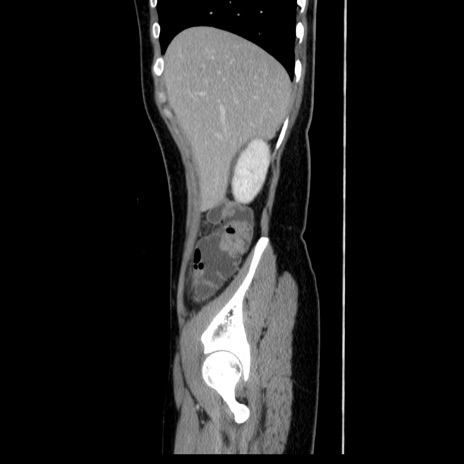

症例39(矢状断像)

【症例】40歳代女性

【主訴】上下腹部痛

【現病歴】2日目から下腹部痛あり。夜間は痛みで眠れなかった。昨日より上腹部痛と下痢が出現。臥位で痛みは軽快したため、休んでいた。本日になって臥位でも立位でも痛みが強くなってきたため救急要請。

【既往歴】子宮内膜症

【身体所見】部:平坦・軟、左上下腹部に圧痛あり、反跳痛あり。

【データ】WBC 21800、CRP 26.78

CT